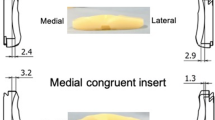

Overall, 63 knees of 55 patients with a mean age of 72.4 ± 8.1 years (range: 45–85 years) were enrolled in the study. The average pre-operative hip–knee–ankle angle was 10.6 ± 5.8° in varus knees. The implants used were NexGen CR-Flex, Persona CR (Zimmer, Warsaw, IN, USA, n = 37), and FINE Total Knee System (Nakashima Medical, Okayama, Japan, n = 26). Further patient characteristics are listed in Table 1. The patients were divided into two groups according to the TKA design concept. NexGen CR-Flex and Persona CR, which induce kinematics to the inherent restraint of implants by adopting the symmetrical surface design of neutral joint-line obliquity between the femoral condyle and the tibial insert, were classified as group S. On the other hand, the anatomical approach that prioritises the kinematics inherent in soft tissues, as the FINE Total Knee System has an asymmetrical design with 3° of joint line obliquity on the insert of the coronal alignment to build in anatomical elements, was classified as group A (Fig. 1) [31, 33]. Both group models adopt multi-radius designs for the femoral component. Meanwhile, there are differences in the radius size between the medial and lateral condyle of group A to reproduce the anatomical joint line. The medial parapatellar approach and measured resection technique were used for all knees. Femoral and tibial joints were resected by mechanical alignment.

The most important finding of the present study is that the difference in the design concept affects midflexion rotational laxity in CR-TKA. The results indicated that the rotational laxity at the initial flexion angle of asymmetrically designed implants had significantly decreased, compared with that of the symmetrically designed implants. FINE Total Knee System was developed to reconstruct an anatomical normal knee; the femoral medial condyle has greater radius than the lateral condyle to reproduce 3° of joint line obliquity in coronal alignment. When combined with the insert, it enhances the conformity of the medial condyle joint surface, and the post-operative analysis of kinematics using image-matching has shown tibial internal rotation with medial pivot motion [31, 33]. Furthermore, several cadaveric studies have indicated that the medial structures such as the superficial medial collateral ligament (sMCL), deep medial collateral ligament (dMCL), and posterior oblique ligament resist tibial internal rotational stress during the early stage of flexion [5, 10, 32, 44, 45]. It is inferred from the previous study that the characteristic of FINE seemingly affects the ligament tension pattern, especially with medial structures. As several researchers have emphasised the importance of medial stability for good clinical outcomes in TKA [20, 41, 46], patient-reported outcome measures remain to be investigated further.